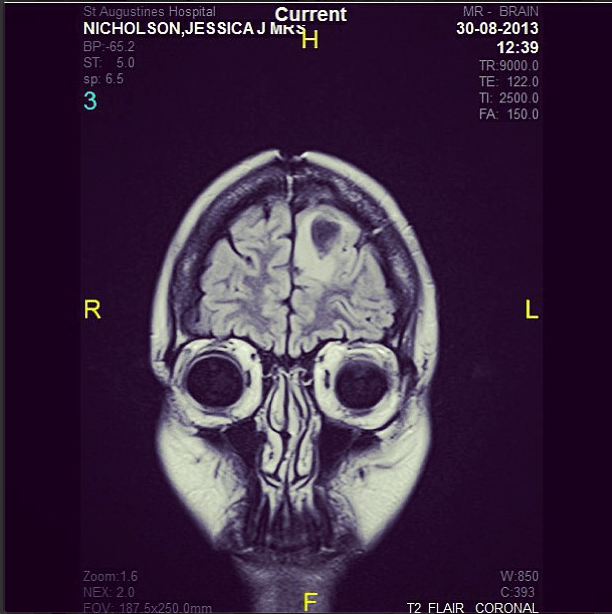

He took us to a computer and showed us the scan results. The tumour was very real. It was the most unnatural thing to see it sitting there, in my wife’s brain. The feeling of disbelief, hopelessness, horror is indescribable.

1. it had a decent outline, no creepy fingers sticking out into other areas.

2. it was 2cm from the surface, very operable by tumour standards.

3. it was still relatively small by glioblastoma standards, 2.6cm x 1.5cm (average blastomas are roughly around 10cm)

We walked back to Jess and put on an oscar winning performance. She was convinced that we were completely chilled. I think. Here is what the bastard thing looked like…that ball is the tumour… the milky white is swelling caused by the tumor. A really bad sign of spreading.

When he pulled up Jess’s scan on the computer, I felt the need to tell him he had the wrong patient. That was not my wife’s brain. It simply couldn’t be. How could I be looking at this picture only 3 months after a clear scan? It is not something I can describe, sitting in a room with the love of your life and listening to a neurosurgeon tell you, “there is nothing left to do”.

We headed out in the ambulance for the last time, 50 minutes to Westville hospital for her MRI. A kind nurse allowed me to sneak a look at the scan as they loaded, it was difficult thing to see, her whole half of her brain had turned white with tumour, but I was so numb from all of this, I didn’t really get too emotional, I knew where we were at. Later that arvo, back in Ballito the neuro sat with us and confirmed what I had seen. The tumours had exploded in 4 weeks, from reducing in size, to covering half of her brain. That is the problem with a Glioblastoma Multiforme, is shape shifts, jumping from one gene to another, which makes it so difficult to treat, what works against it for a few weeks, becomes useless as it jumps to the next gene.